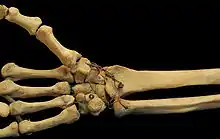

In human anatomy, the wrist is variously defined as (1) the carpus or carpal bones, the complex of eight bones forming the proximal skeletal segment of the hand;[1][2] (2) the wrist joint or radiocarpal joint, the joint between the radius and the carpus[2] and; (3) the anatomical region surrounding the carpus including the distal parts of the bones of the forearm and the proximal parts of the metacarpus or five metacarpal bones and the series of joints between these bones, thus referred to as wrist joints.[3][4] This region also includes the carpal tunnel, the anatomical snuff box, bracelet lines, the flexor retinaculum, and the extensor retinaculum.

Carpal bones of the hand:

- Proximal: A=Scaphoid, B=Lunate, C=Triquetrum, D=Pisiform

- Distal: E=Trapezium, F=Trapezoid, G=Capitate, H=Hamate

In the hand proper a total of 13 bones form part of the wrist: eight carpal bones—scaphoid, lunate, triquetral, pisiform, trapezium, trapezoid, capitate, and hamate— and five metacarpal bones—the first, second, third, fourth, and fifth metacarpal bones.[8]